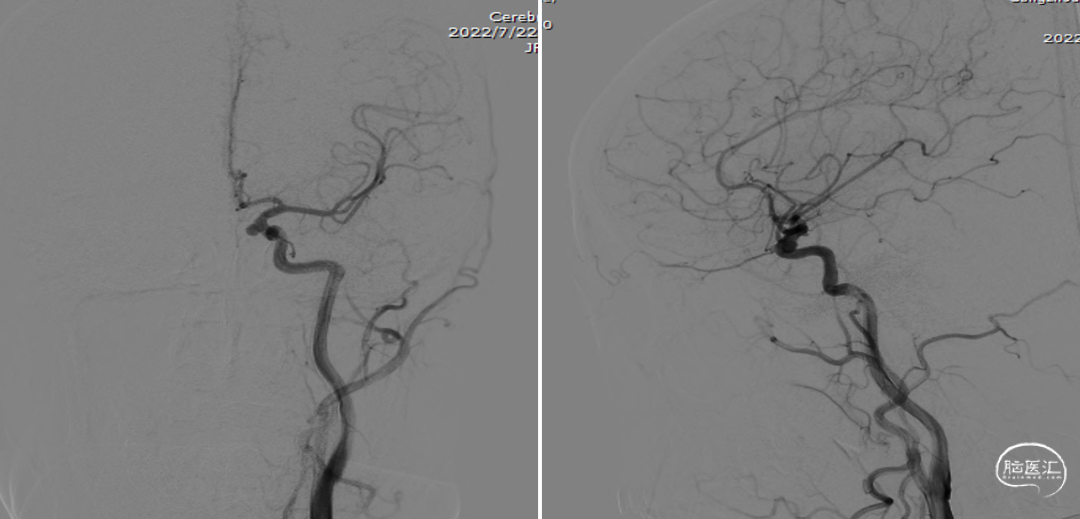

全脑血管造影(2022-07-22)

左颈内动脉3D重建图像(4.6mm*4.9mm)